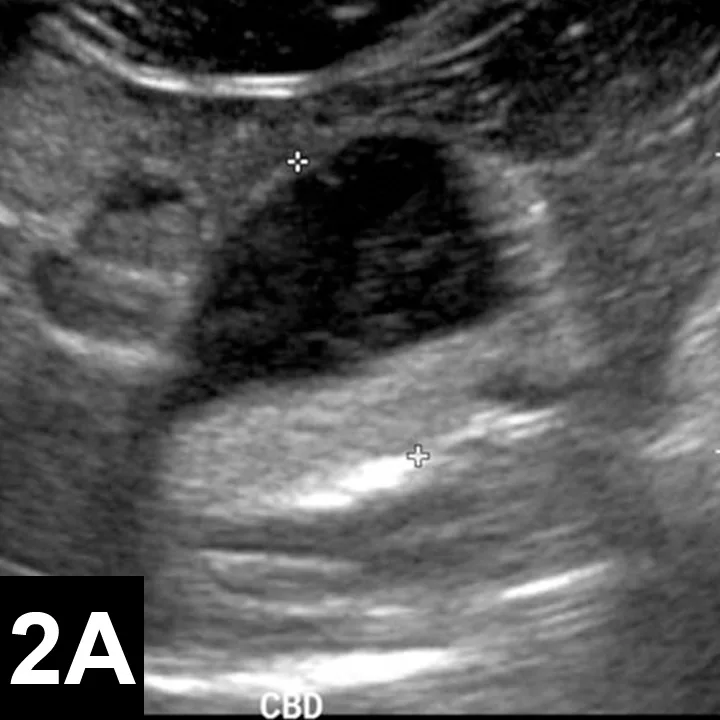

• Animals with choledochal cysts (Figure 2) often present with secondary bacterial infections.16

Figure 2. Ultrasonography showing choledochal cysts in a domestic short-haired cat (5 years of age, A). The cat’s common bile duct (CBD) was greatly enlarged (cursors) and half filled with echogenic sediment. On previous ultrasounds, the CBD had been mistaken for the gallbladder and a hepatic abscess. The cat had recurrent bacterial cholecystitis until the malformation was surgically corrected. In a 10-month-old dog (B), the CBD is distended with echogenic walls. This dog also had gallbladder agenesis and congenital hepatic fibrosis. Bile culture was negative.